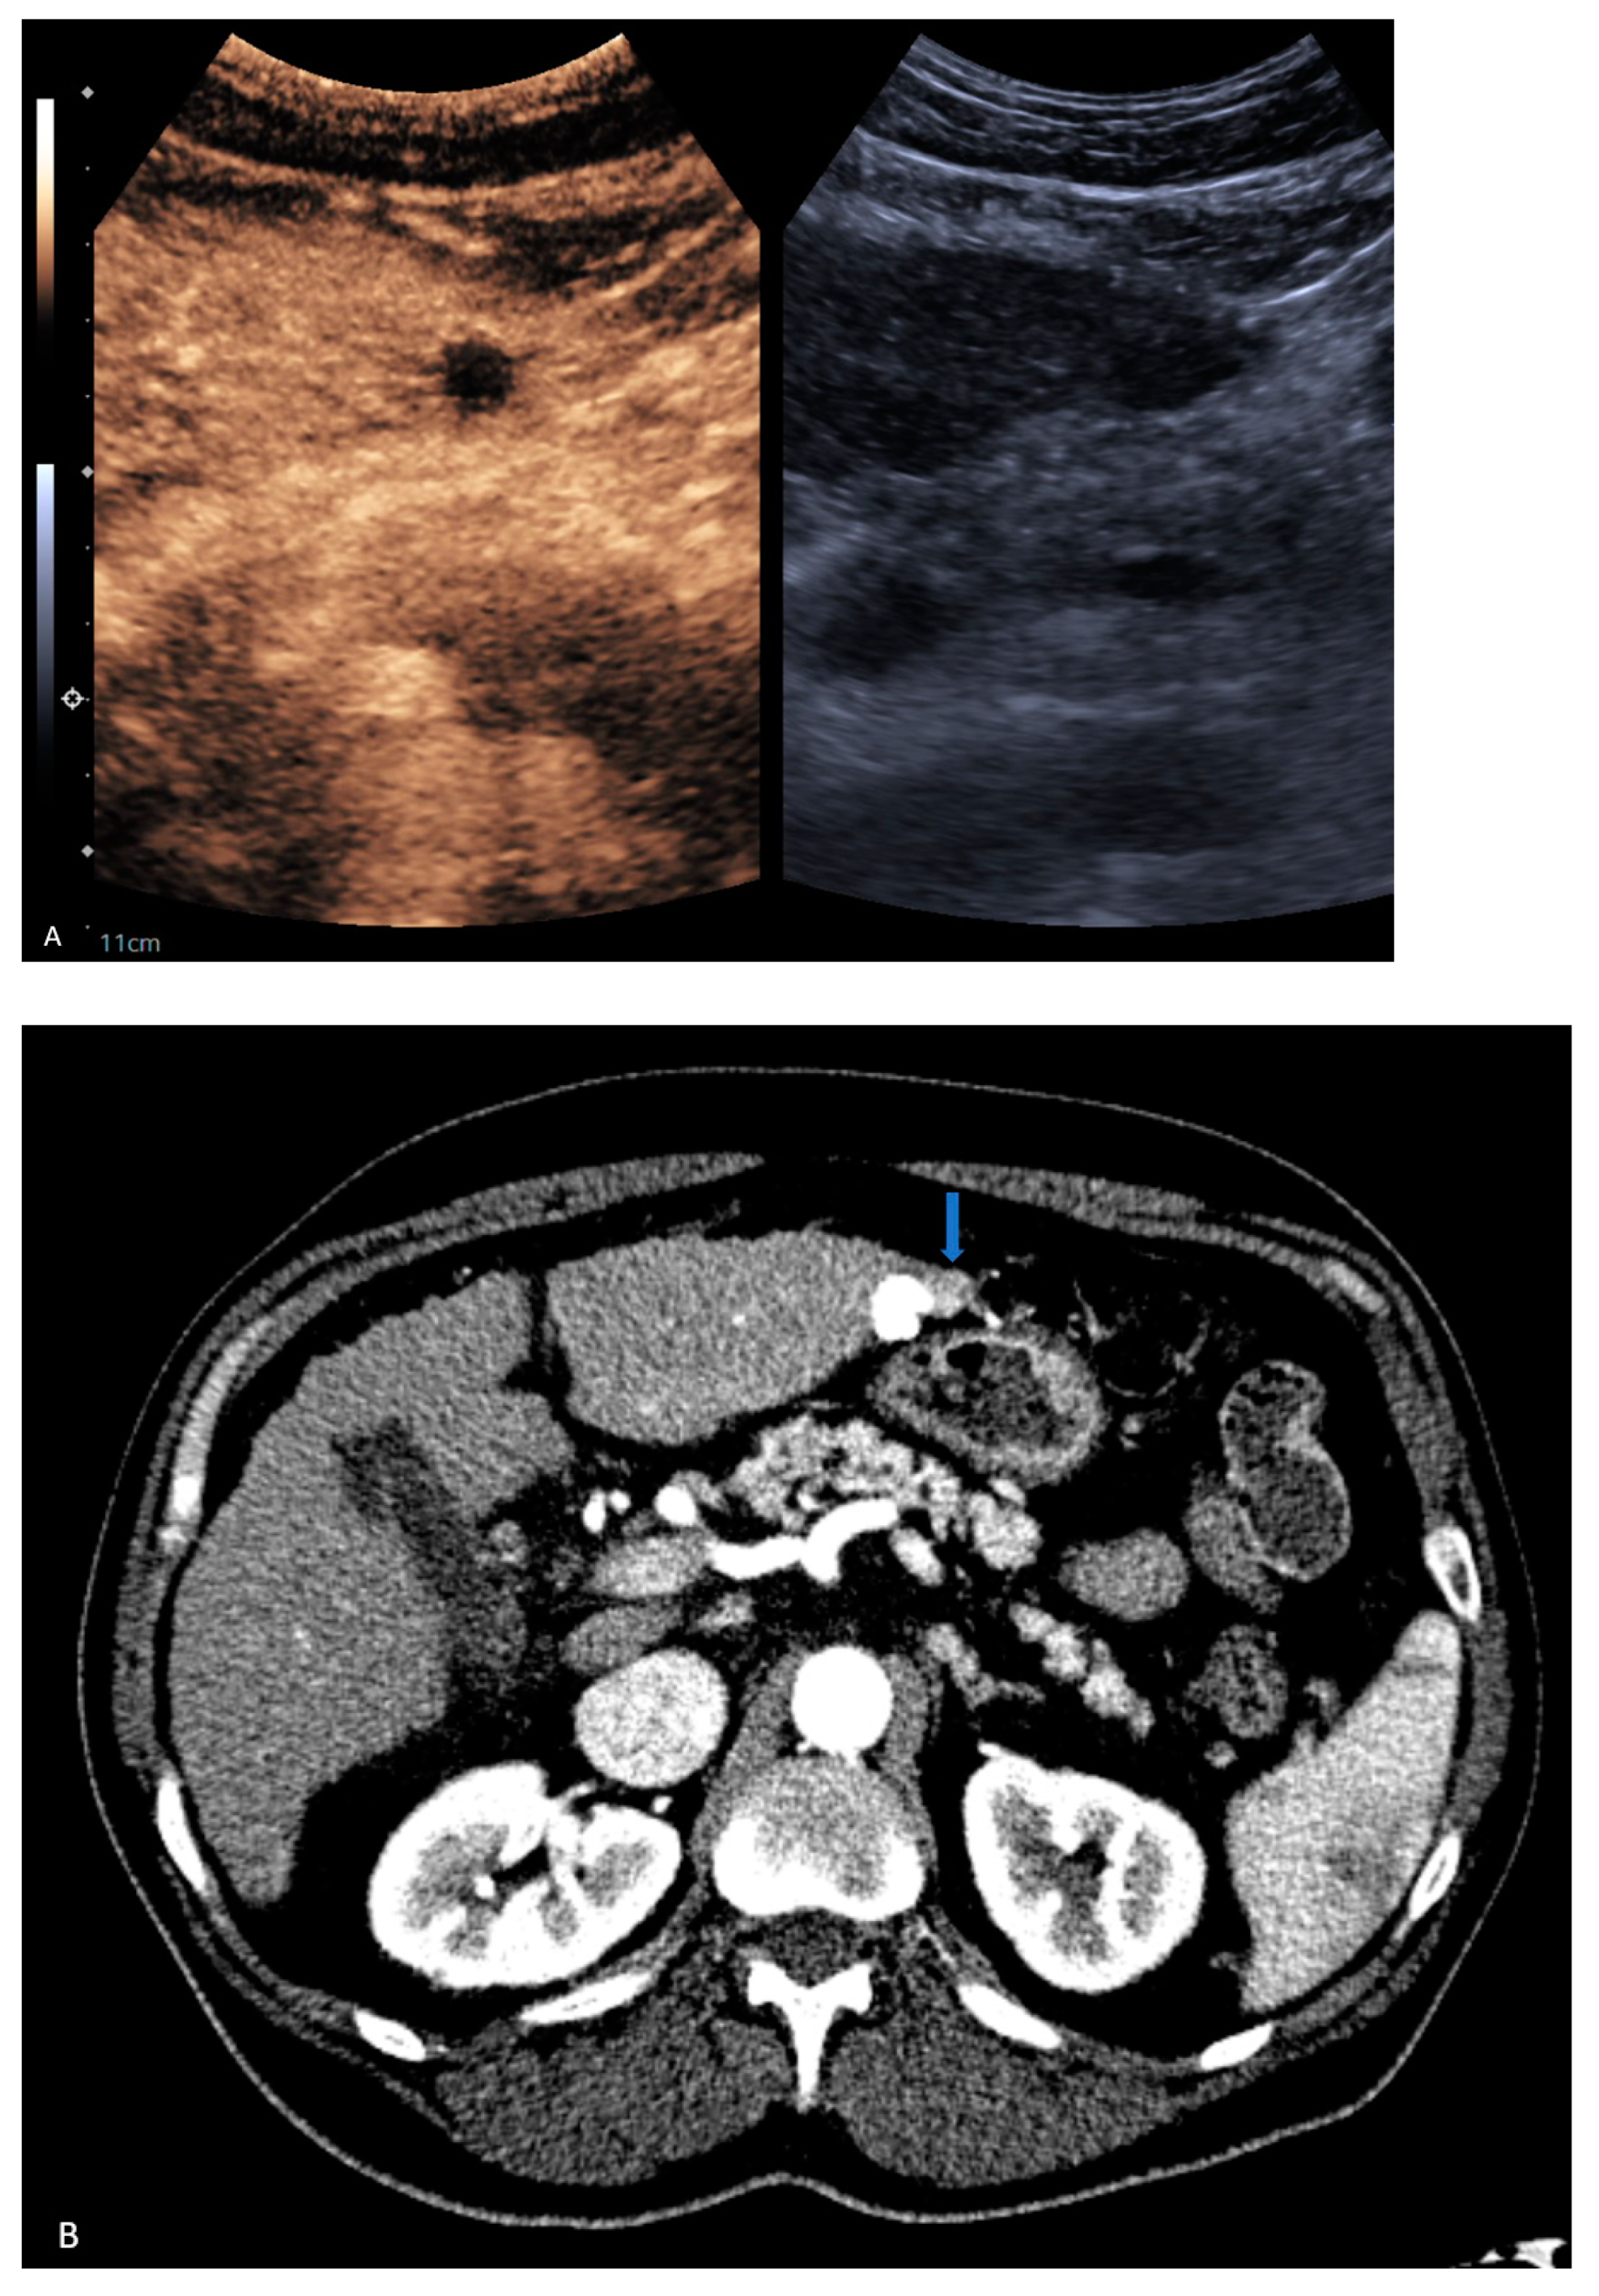

| 7 | CEUS | Target | LR-treated | CT called residual tumor, follow-up CT showed the area was perfusional, not disease (Figure 3) |